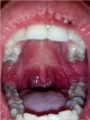

У меня такой вопрос: в верхнем ряду напухла десна, недавно была на проф. осмотре у стоматолога, он смотрел полость рта, но ничего не сказал. А зуб самый последний, похоже 8. Сама спросить как-то побоялась.

Как мне быть, снова идти спрашивать, или можно как-то пополоскать?

Полоскать Вы, конечно, можете, но это не лечение. Отёчность говорит о воспалительном процессе, и без врача Вам не справиться.